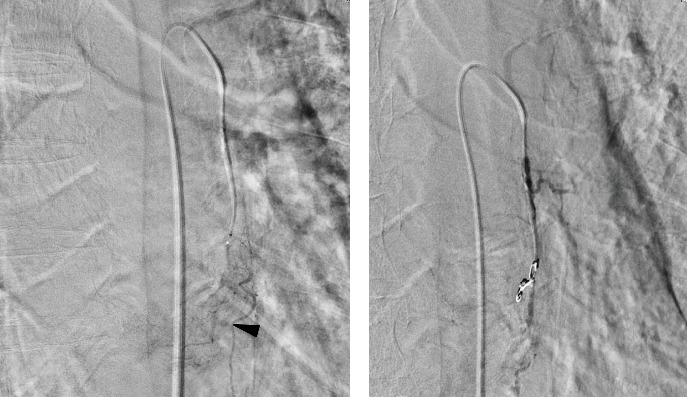

Esophageal bleeding management typically involves endoscopy but becomes challenging with large or hemorrhagic tumors, especially in cases of rare basal cell carcinoma. This malignancy, with a poorer prognosis than squamous cell carcinoma, often requires definitive surgery. A 78-year-old man with severe hematemesis underwent transarterial embolization (TAE) after failed endoscopic hemostasis for a middle thoracic esophageal tumor. Subsequently, he successfully underwent radical tumor resection on the seventh day of hospitalization. While emergency surgery is an option, its invasiveness may be a limitation, especially for patients in poor general condition. TAE is effective for hemostasis and serves as a crucial bridge to radical esophageal tumor resection.